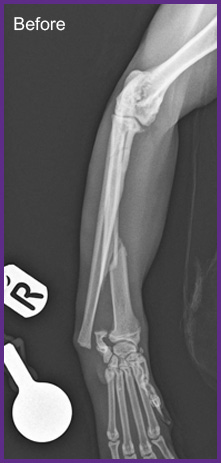

We offer general medical and surgical services with advanced diagnostic facilities. Also, we are one of the few clinics in Hong Kong that provide both CT Scan and MRI services for animals. Our team are equipped to provide detail nursing care for hospitalize pets.